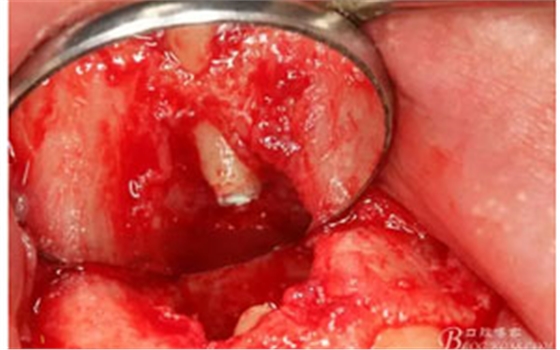

圖8.從垂直切口和水平切口的連接處翻瓣。發(fā)現(xiàn)11和12之間的骨壁有缺損。

圖9.翻開角形瓣后,有骨壁缺損,囊壁有穿孔,這就是溢膿的竇道出口。

圖10。用骨膜剝離器沿著骨壁、緩慢逐漸剝離囊壁。

圖13.囊壁摘除后形成的骨腔,12牙根完全裸露在骨腔內(nèi)。